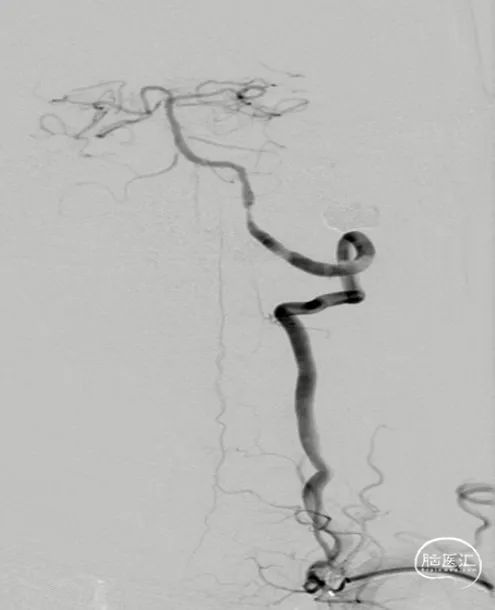

外院DSA(2023.02.09):左侧椎动脉V4段重度狭窄,右侧椎动脉V3段远端闭塞。前循环未见明显异常。

术前造影